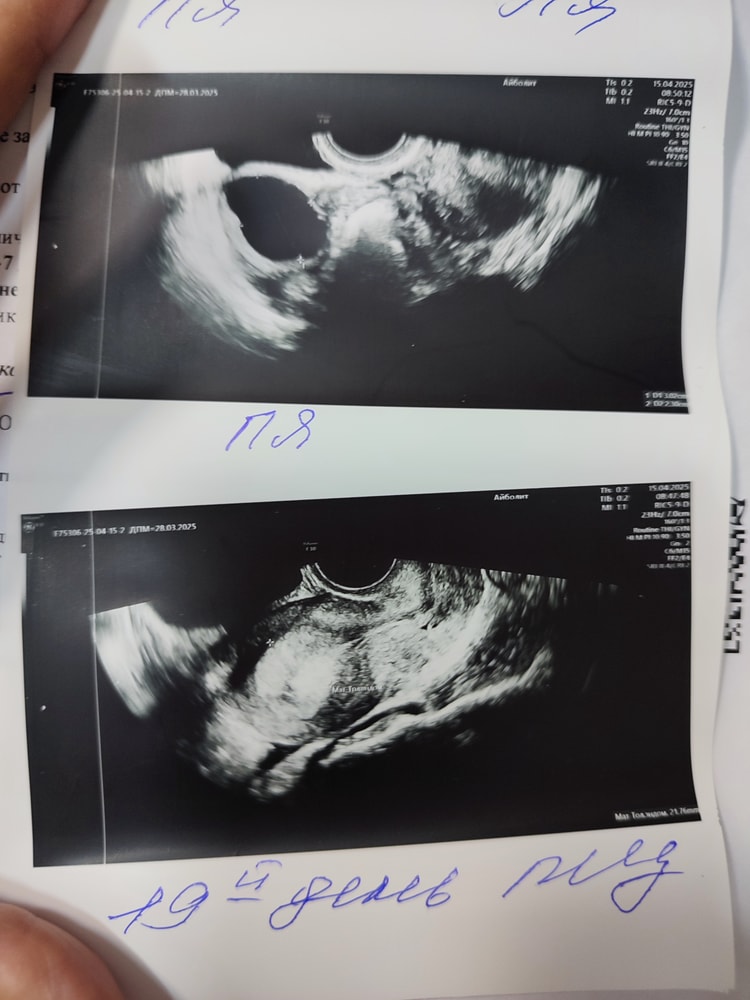

Эндометрий 21.7 мм и киста

Ктр в 8 недель. УЗИ на сроке 5-6 недель